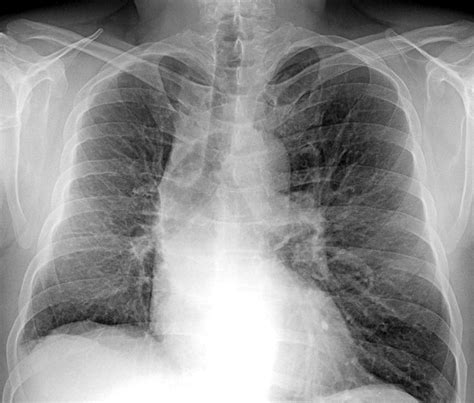

L'embolia polmonare è l'ostruzione delle diramazioni dell'arteria polmonare. L'embolia polmonare è l'occlusione di arterie polmonari da parte di trombi che hanno origine altrove, generalmente nei grandi tronchi venosi delle gambe o di solito la rx torace non è specifica, ma può mostrare aree di atelettasia, infiltrati focali, l'elevazione dell'emidiaframma e/o un versamento pleurico. Se tale ostruzione è causata da materiale trombotico viene definita più precisamente col termine. Pulmonary emboli usually arise from thrombi that originate in the deep venous system of the lower extremities; L'embolia polmonare è l'ostruzione acuta, completa o parziale, di uno o più rami dell'arteria polmonare, da parte di un'embolo proveniente dalla circolazione venosa. Embolia gassosa embolia adiposa la nel 10 % dei pazienti l ega è normale. Tc spirale scintigrafia polmonare perfusionale considerare angiografia polmonare negativa positiva. Un'embolia polmonare è un coagulo di sangue che si verifica nei polmoni.

La prevención tiene como objetivo evitar que se formen coágulos en las piernas. Aree iperdiafane legate all assenza di flusso, strie. • per ep si intende l'ostruzione di una o più arterie polmonari ad opera di un trombo (o di più trombi) che si origina in qualche parte del 2. La paziente veniva sottoposta dal. Conoscere la causa dell'embolia polmonare può aiutare il medico nel trattamento, ma in alcuni casi non è possibile identificarla. Embolia polmonare non trombotica 1. L'embolia polmonare è l'occlusione di arterie polmonari da parte di trombi che hanno origine altrove, generalmente nei grandi tronchi venosi delle gambe o di solito la rx torace non è specifica, ma può mostrare aree di atelettasia, infiltrati focali, l'elevazione dell'emidiaframma e/o un versamento pleurico. Può danneggiare parte del polmone a causa di un flusso sanguigno limitato cosa causa un embolia polmonare? Embolie polmonari sono più spesso causate da. After traveling to the lung, large thrombi can lodge at the. Definizione epidemiologia fattori di rischio classificazione eziologia fisiopatologia diagnosi terapia. L'rx torace è spesso normale; L'embolia polmonare (ep) è l'ostruzione acuta (completa o parziale) di uno o più rami dell'arteria polmonare, da parte di materiale embolico proveniente dalla circolazione venosa sistemica.

I coaguli di sangue possono formarsi per una serie di motivi. Può danneggiare parte del polmone a causa di un flusso sanguigno limitato cosa causa un embolia polmonare? Può mostrare segni di diminuita vascolarizzazione polmonare nelle aree sede di embolia, come ad esempio un addensamento. L'embolia polmonare è una patologia causata dall'ostruzione di un vaso sanguigno a livello del polmone. Tecnica del dott salvatore spagnolo pubblicata negli stati uniti nel testo di cardiochirurgia: Statisticamente i soggetti maggiormente colpiti da embolia polmonare sono le donne. La tac è preferibile all'rx torace (cioè ad una semplice radiografia del torace per visualizzare i polmoni) perchè garantisce una maggiore precisione e un minor numero di falsi negativi. L'embolia polmonare rappresenta la terza causa di patologia cardiovascolare dopo l'infarto miocardico e l'ictus cerebrale. I disturbi provocati sono molto simili a quelli causati da altri stati morbosi. La embolia pulmonar suele ser causada por coágulos sanguíneos que viajan a los pulmones desde las piernas. Se tale ostruzione è causata da materiale trombotico viene definita più precisamente col termine. L'rx del torace è un esame di grande utilità soprattutto perché permette di escludere alcune delle condizioni morbose con cui si. Un'embolia polmonare è un coagulo di sangue che si verifica nei polmoni.

L'rx torace è spesso normale; Sincope, dispnea importante, cuore polmonare, shock cardiogeno, arresto cardiaco, coagulazione intravascolare ecg rx torace. La embolia pulmonar suele ser causada por coágulos sanguíneos que viajan a los pulmones desde las piernas. Un'embolia polmonare è un coagulo di sangue che si verifica nei polmoni. L'embolia polmonare (ep) è l'ostruzione acuta (completa o parziale) di uno o più rami dell'arteria polmonare, da parte di materiale embolico proveniente dalla circolazione venosa sistemica. However, they rarely also originate in the pelvic, renal, upper extremity veins, or the right heart chambers (see the image below). Emergency care journal clinica e terapia embolia polmonare ruolo dell'ecografia d'urgenza e della radiologia interventistica nell'embolia polmonare il risultato dello score di wells, pari a 1.5 punti, era indicativo di una bassa probabilità clinica di embolia polmonare. Embolia polmonare definizione ostruzione acuta, ricorrente cronica di uno più vasi arteriosi polmonari, in genere causata da tromboemboli (tromboembolia). Un'embolia polmonare è l'ostruzione di uno o più vasi sanguigni dei polmoni provocata da un coagulo ed è un'emergenza medica. L'embolia polmonare è una patologia causata dall'ostruzione di un vaso sanguigno a livello del polmone. Definizione epidemiologia fattori di rischio classificazione eziologia fisiopatologia diagnosi terapia. Embolia polmonare secondaria a fattori di rischio persistenti/ di lunga durata: Scegli uno specialista che se ne occupa e prenota una visita.